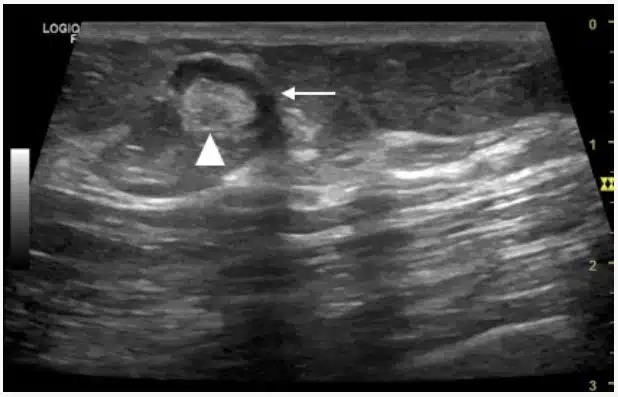

Como é um linfonodo maligno no ultrassom?

O ultrassom com Doppler é o principal exame inicial para avaliação dos linfonodos, permitindo diferenciar achados benignos de suspeitos.

🔹 Características ultrassonográficas de malignidade

Formato arredondado (relação eixo longo/eixo curto < 2)

Perda ou ausência do hilo gorduroso

Contornos irregulares ou mal definidos

Ecotextura heterogênea

Áreas de necrose interna

Calcificações (em alguns tumores)

Vascularização periférica ou caótica ao Doppler

Aumento do eixo curto (mais relevante que o tamanho total)

📌 A perda do hilo gorduroso é um dos achados mais importantes.

Diferença entre linfonodo benigno e maligno no ultrassom

Característica Benigno Maligno

Formato Oval Arredondado

Hilo gorduroso Preservado Ausente

Contornos Regulares Irregulares

Ecotextura Homogênea Heterogênea

Vascularização Central (hilar) Periférica/caótica

Mobilidade Preservada Reduzida